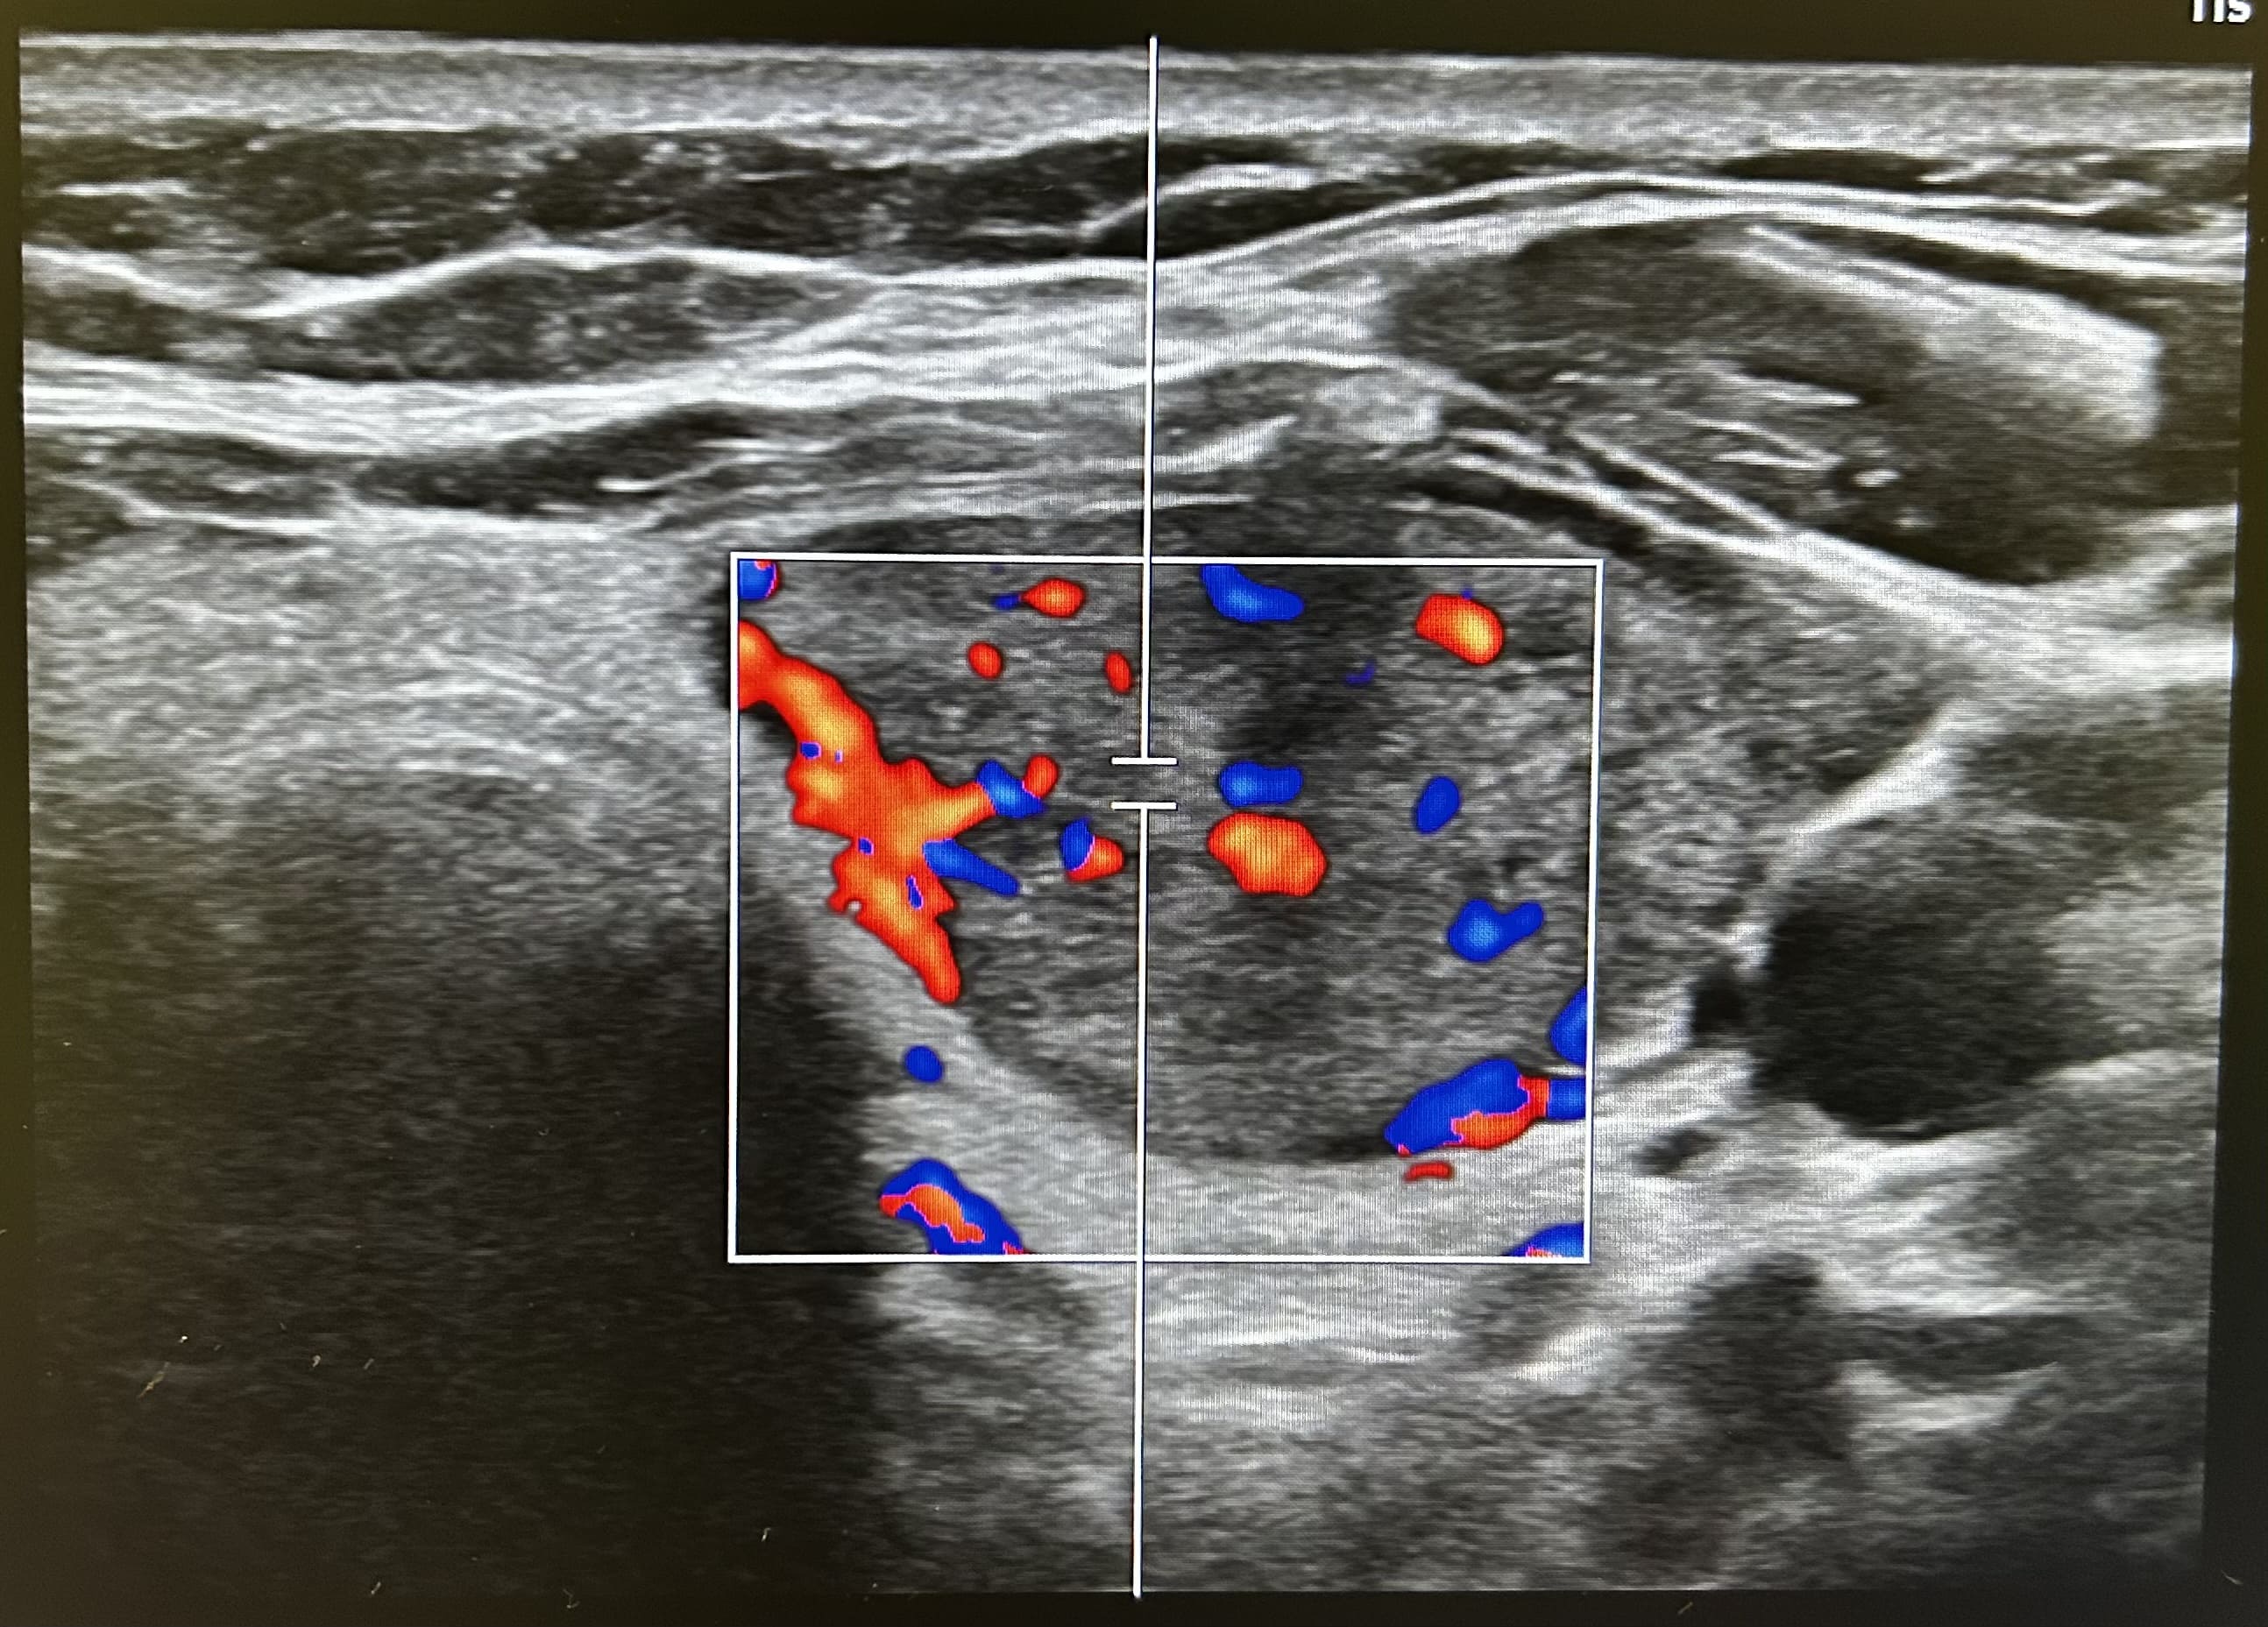

Apreciamos un nódulo tiroideo hipoecogénico y heterogéneo, de bordes irregulares y con vascularización central de 22 milímetros de diámetro mayor (transversal). Sin apreciar microcalcificaciones ni invasión de la glándula. No apreciamos adenopatías cervicales en rango patológico.

En ecografía reglada describen características similares con un TI-RADS 4, nódulo sugestivo de malignidad.